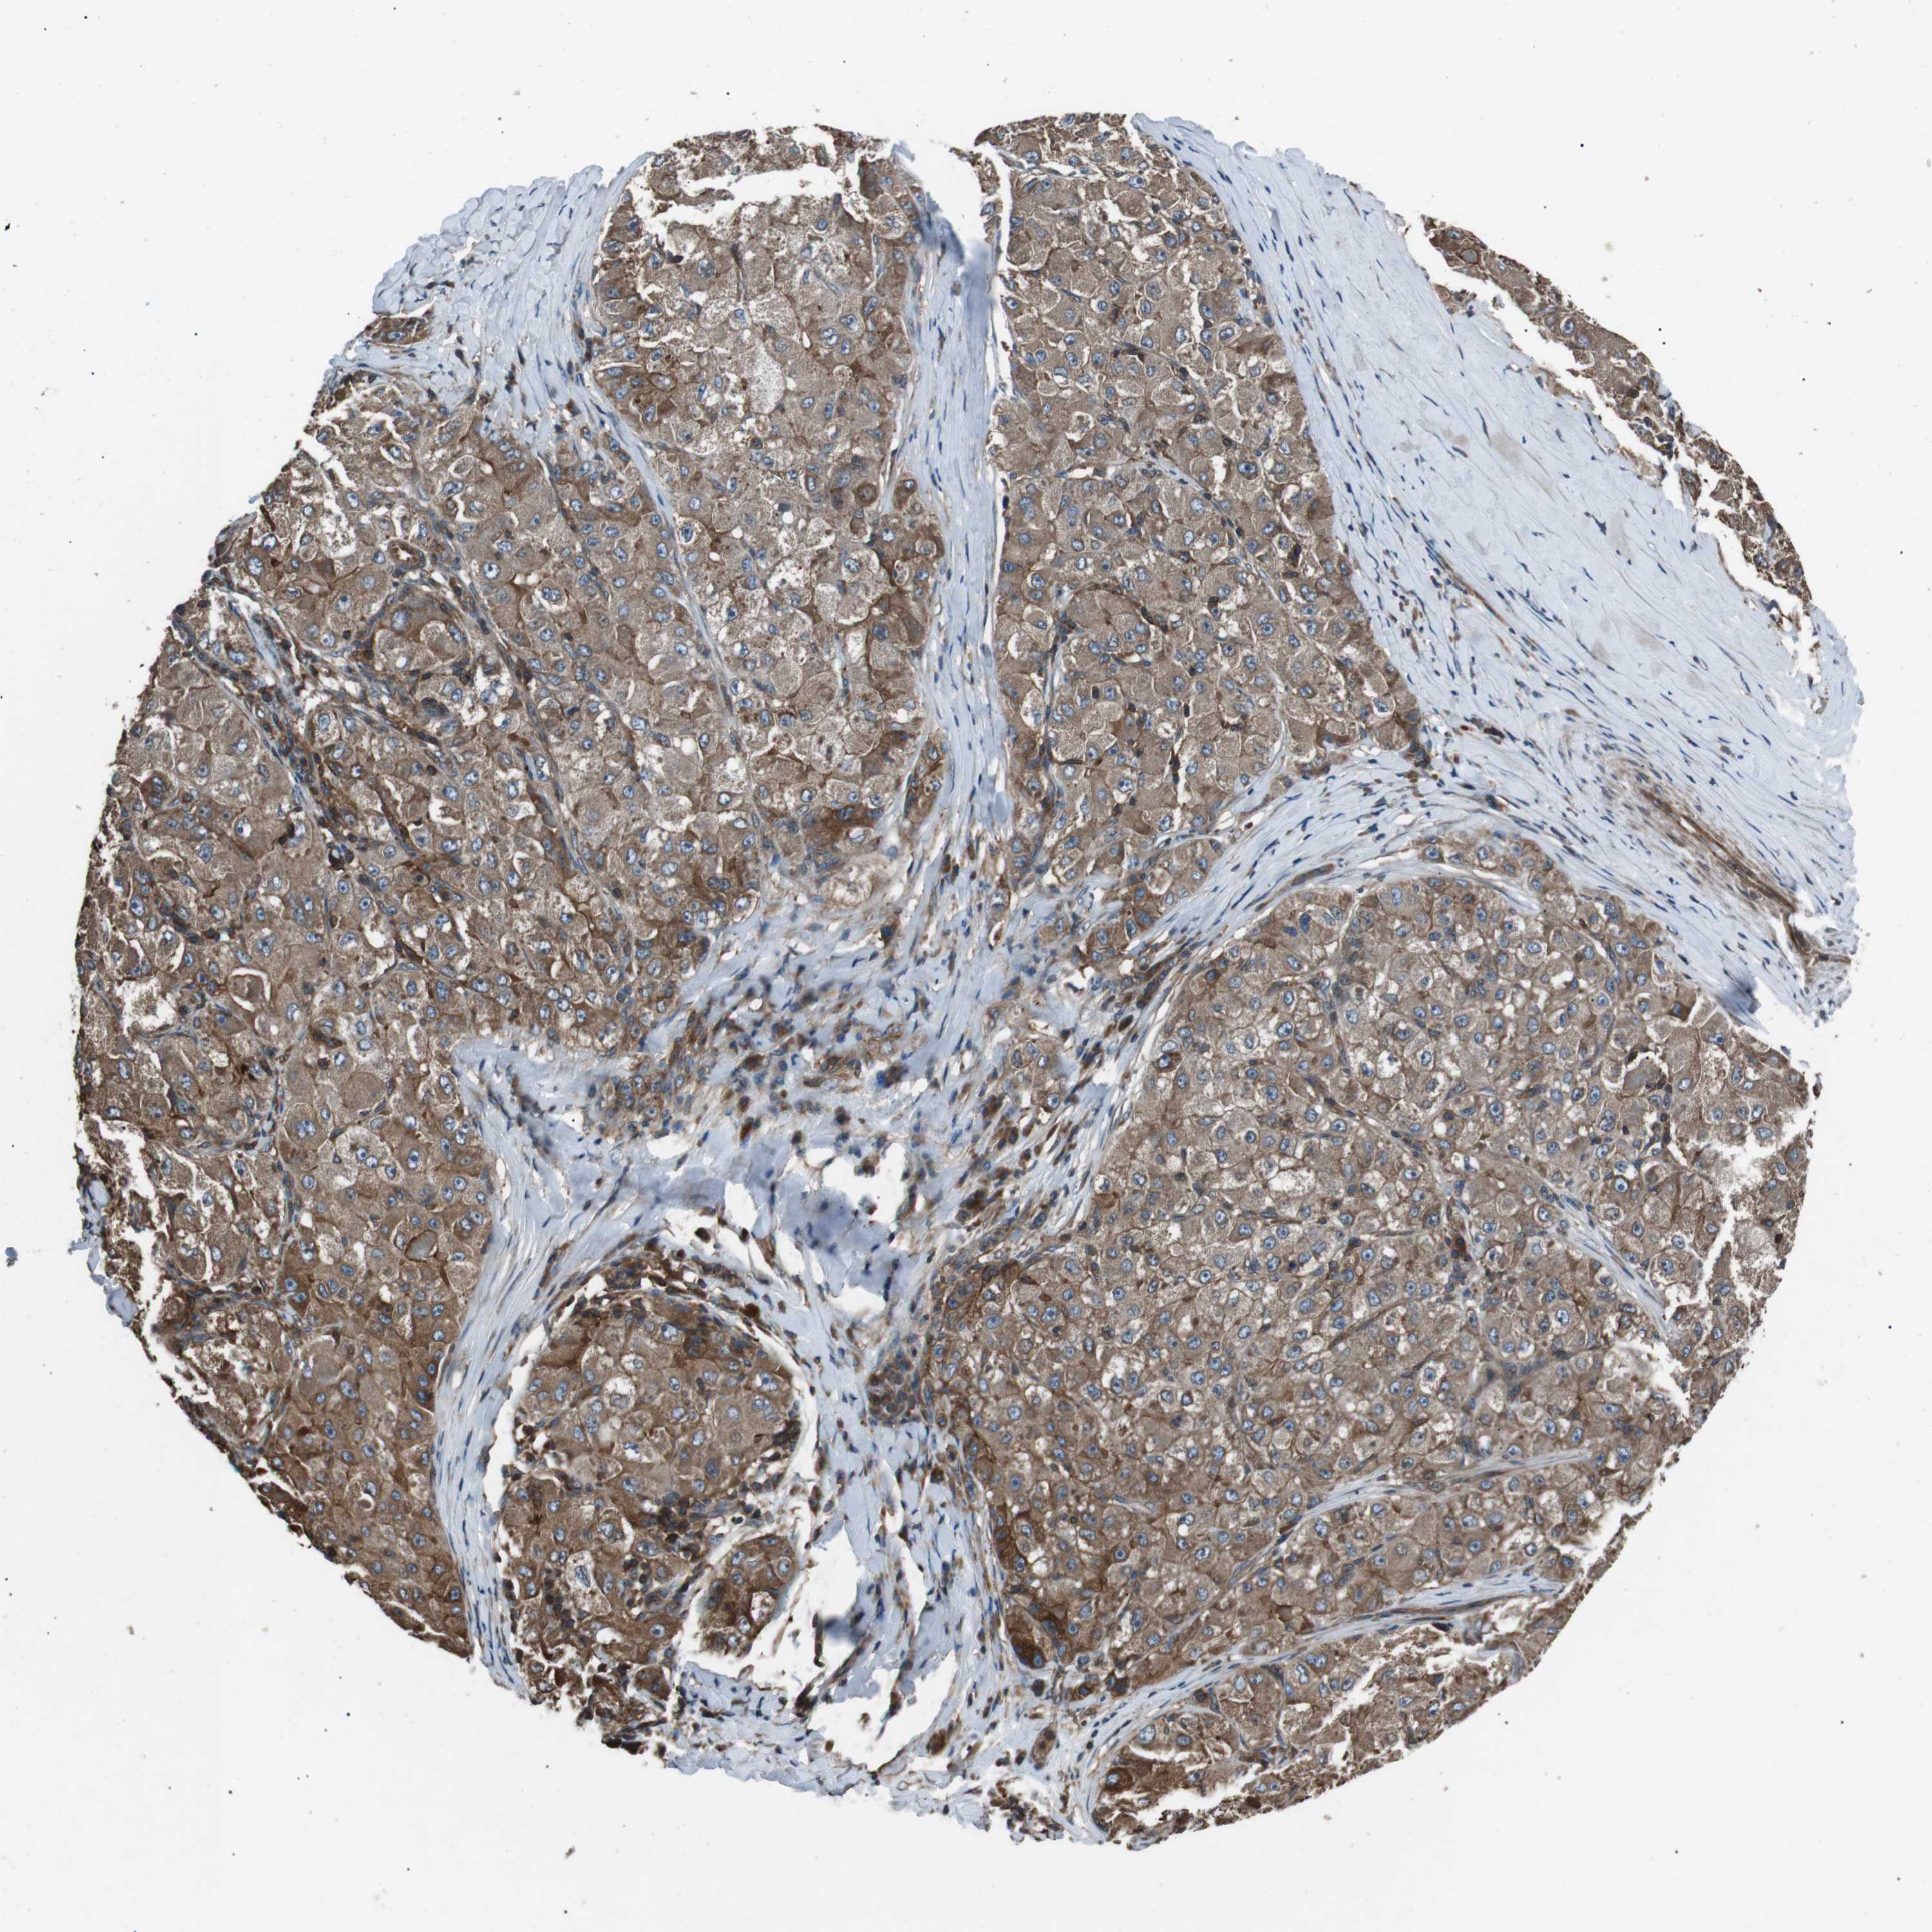

LIVER CANCER - Protein expressioni

A mouse-over function shows sample information and annotation data. Click on an image to view it in a full screen mode. Samples can be filtered based on level of antibody staining by selecting one or several of the following categories: high, medium, low and not detected. The assay and annotation is described here.

Note that samples used for immunohistochemistry by the Human Protein Atlas do not correspond to samples in the TCGA dataset.

Antibody stainingi

Antibody staining in the annotated cell types in the current human tissue is reported as not detected, low, medium, or high, based on conventional immunohistochemistry profiling in selected tissues. This score is based on the combination of the staining intensity and fraction of stained cells.

Each image is clickable and will lead to virtual microscopy that enables deeper exploration of all samples and also displays staining intensity scores, fraction scores and subcellular localization as well as patient and tissue information for each sample.

Antibody HPA015576

Staining

High

Medium

Low

Not detected

Intensity

Strong

Moderate

Weak

Negative

Quantity

>75%

75%-25%

<25%

None

Location

Nuclear

Cytoplasmic/membranous

Cytoplasmic/membranous,nuclear

Cholangiocarcinoma

Carcinoma, Hepatocellular, NOS